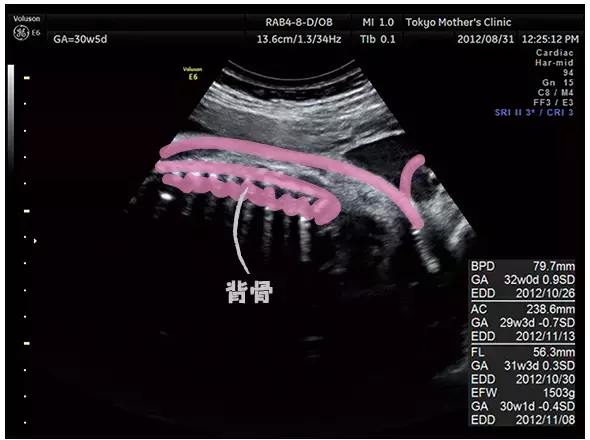

妊娠30週のエコー写真

背骨のそりなどに異常がないかもはっきりと見えるように。

体の機能がほぼ完成する時期。赤ちゃんの大きさなど発育に個人差が出始める頃でもあります。ただし、超音波検査で出すのはあくまでも推定体重で、実際よりも誤差は大きいもの。数値そのものより、前回よりその時期に合った増え方をしているかの推移を先生はチェックしているそうです。